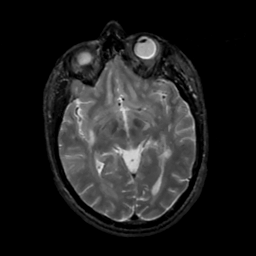

MR Study #5, March 10, 1991 -- Slice #24

[Home][Help][Clinical][Tour 1][Tour 2] Slice 24